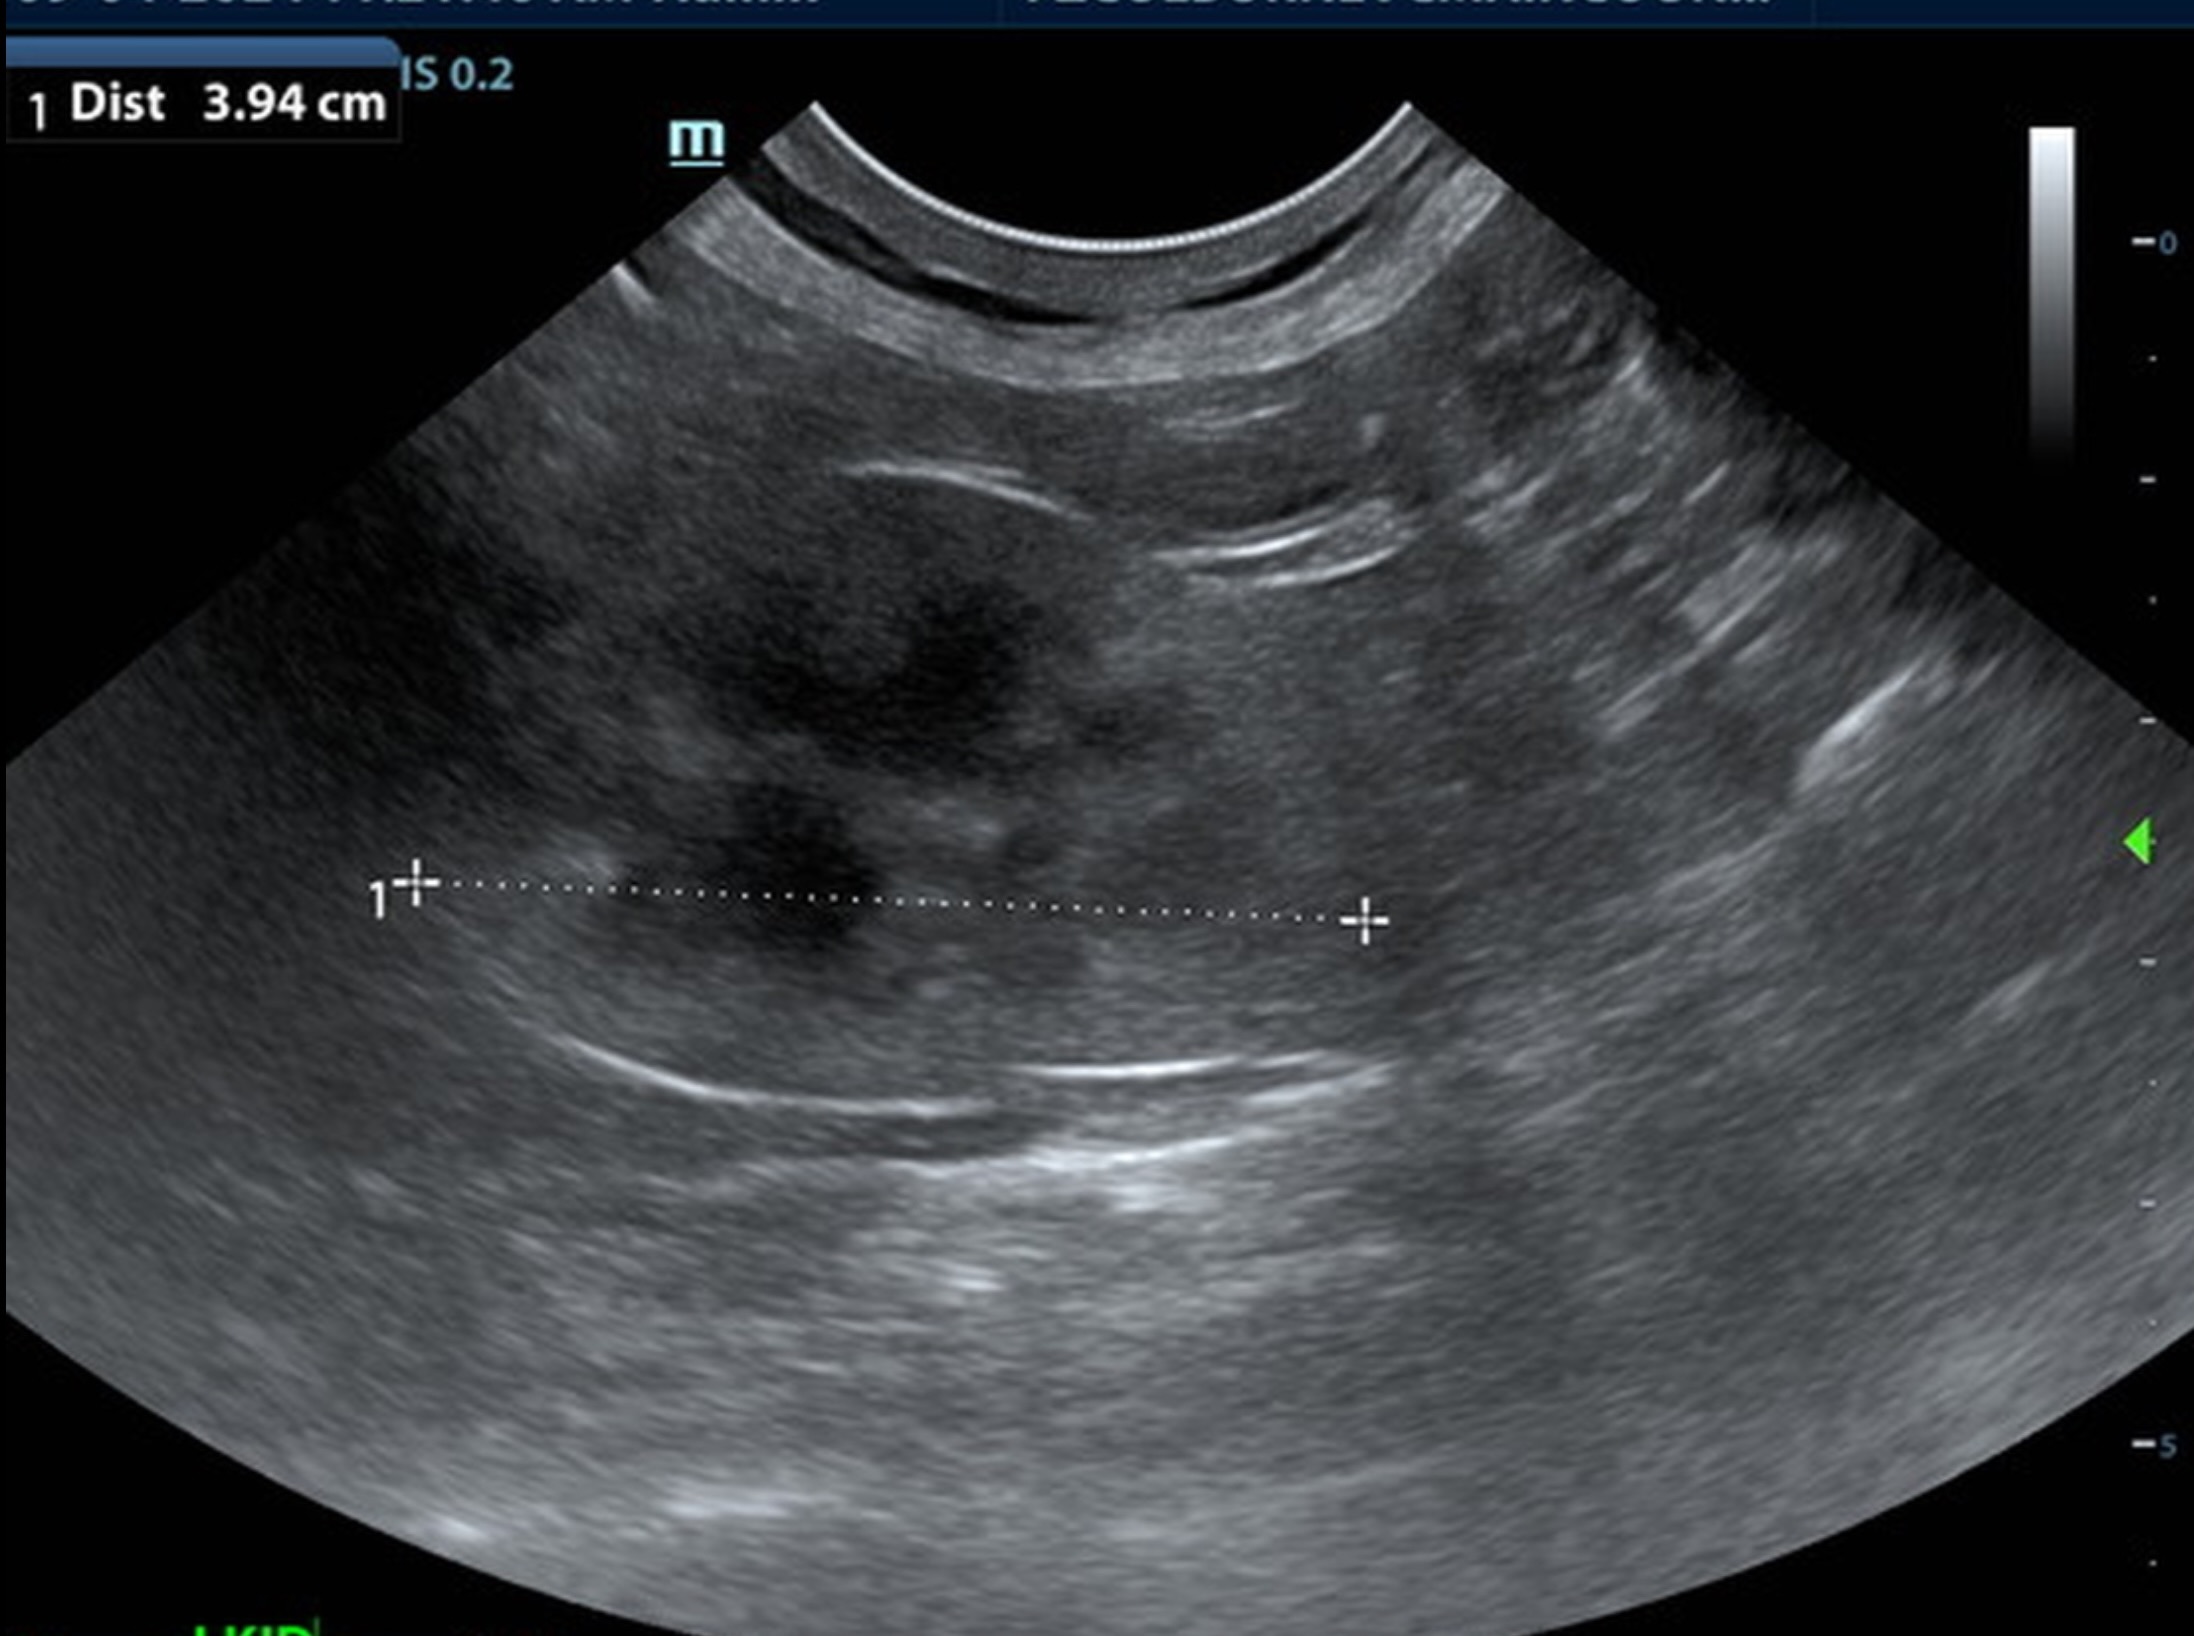

A 6.5 cm hypoechoic abscess was noted in the region of the left pancreatic limb with hyperechoic granulation bed and regional inflammation. The abscess was largely non-vascular. One minor portion of color flow uptake noted within the abscess.

• Large left-sided pancreatic abscess.